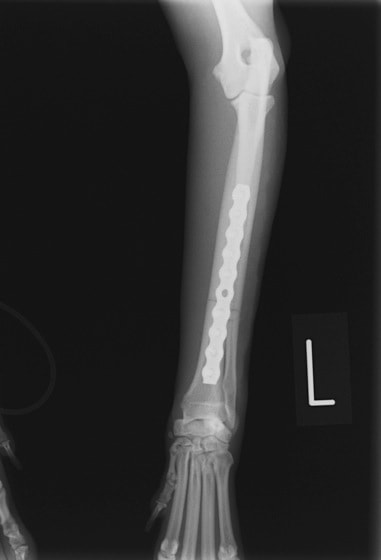

トイプードル 右遠位橈尺骨短斜骨折のALPSによる内固定

Locking Compression Plate

LCPは、スクリュー(ネジ)とプレート(金属の板)をロックする特殊な構造により骨折部位を固定する新しい世代のプレートシステムです。ひとつのホールでロッキングスクリューとスタンダードスクリューの使用を選択できるユニークな構造をしているため、骨折断端間の圧迫を目的とした従来型プレート固定法に加え、高い角度安定性を有するロッキングスクリューを用いた固定法の選択が可能です。従来のプレートシステムでは困難だった部分の骨折や癒合不全の症例に高い治療効果をもたらします。